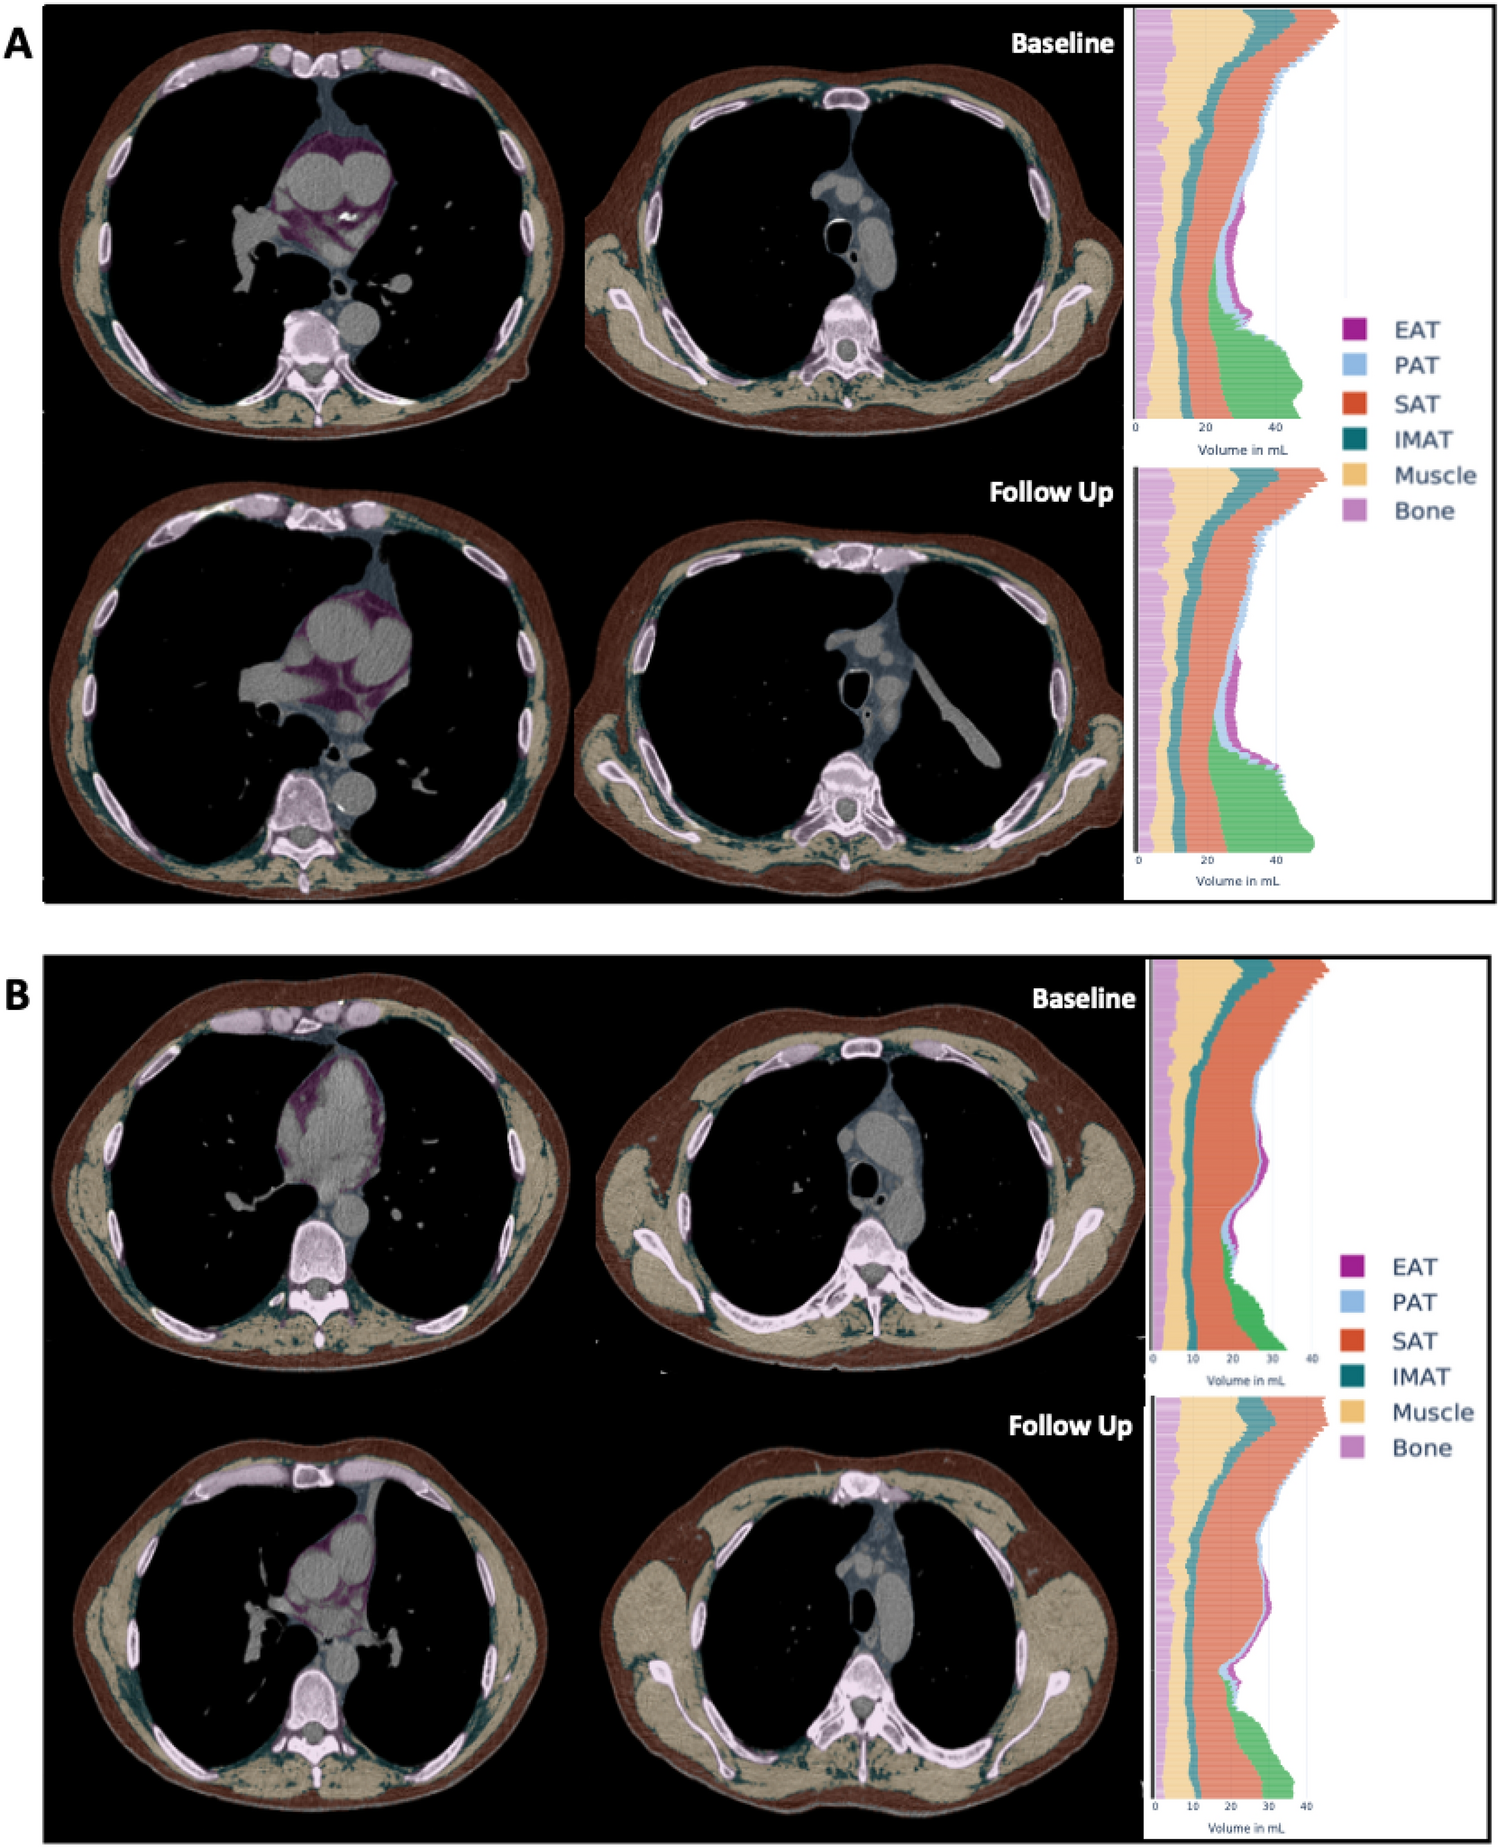

Figure 1

Exemplary outputs of a fully automated CT-based body composition analysis (BCA) before and after BLVR. The BCA network detects various BCA features within the chest CT scan, which are combined with bone volume to calculate body size-adjusted biomarkers. Individual volume distribution is graphically presented. Tissues are marked by colors: pink for bone, yellow for muscle, orange-brown for subcutaneous adipose tissue (SAT), purple for epicardial adipose tissue (EAT), blue for paracardial adipose tissue (PAT), and turquoise for inter- and intramuscular adipose tissue (IMAT). Shown here is an illustrative analysis comparing a patient with a decrease in muscle volume (A) to another patient with an increase in muscle volume (B). Visceral adipose tissue (VAT), represented in green, was not included in this analysis due to variations in the abdominal area covered by the scans among patients.